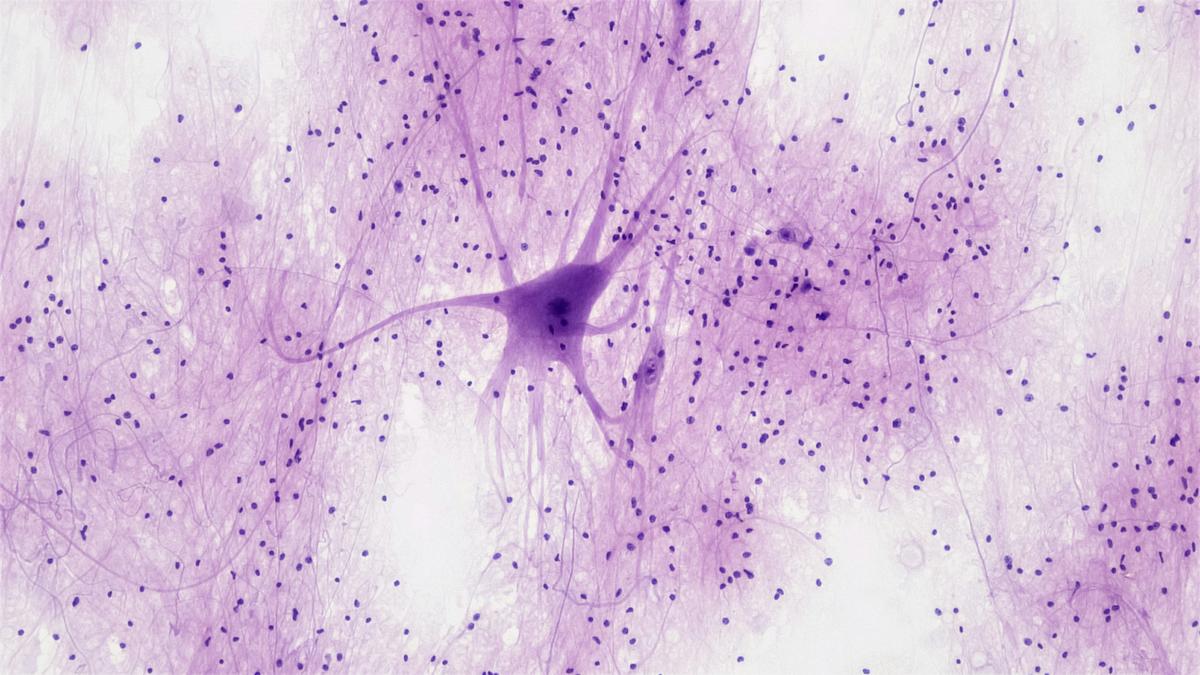

A new study in Science now promises to kick this dust up all over again: it has reported evidence of neural progenitor cells and young neurons — which are the intermediate stages of cellular development — in the hippocampus, the memory centre of adult human brains.

The researchers isolated more than 4,00,000 neurons from the hippocampal region of post-mortem brain samples from (deceased) individuals aged less than a year to 78 years. Then they analysed them using a technique called single nuclei RNA sequencing, which provides a near-complete signature of genes that are expressed (or turned on) in each cell.

“What we know from mouse models is that, typically, there are stem cells which every now and then get activated, proliferate to produce more intermediate progenitors, which also divide extensively,” Ionut Dumitru, one of the first authors of the study and a research specialist at Karolinska, said. “Those that survive become what we call neuroblasts — very young neurons.”

In the study, the team was able to identify all three types of intermediate neuronal stages — neural stem cells, neural progenitors, and neuroblasts — using the machine learning algorithm even in adolescent and adult brain samples.